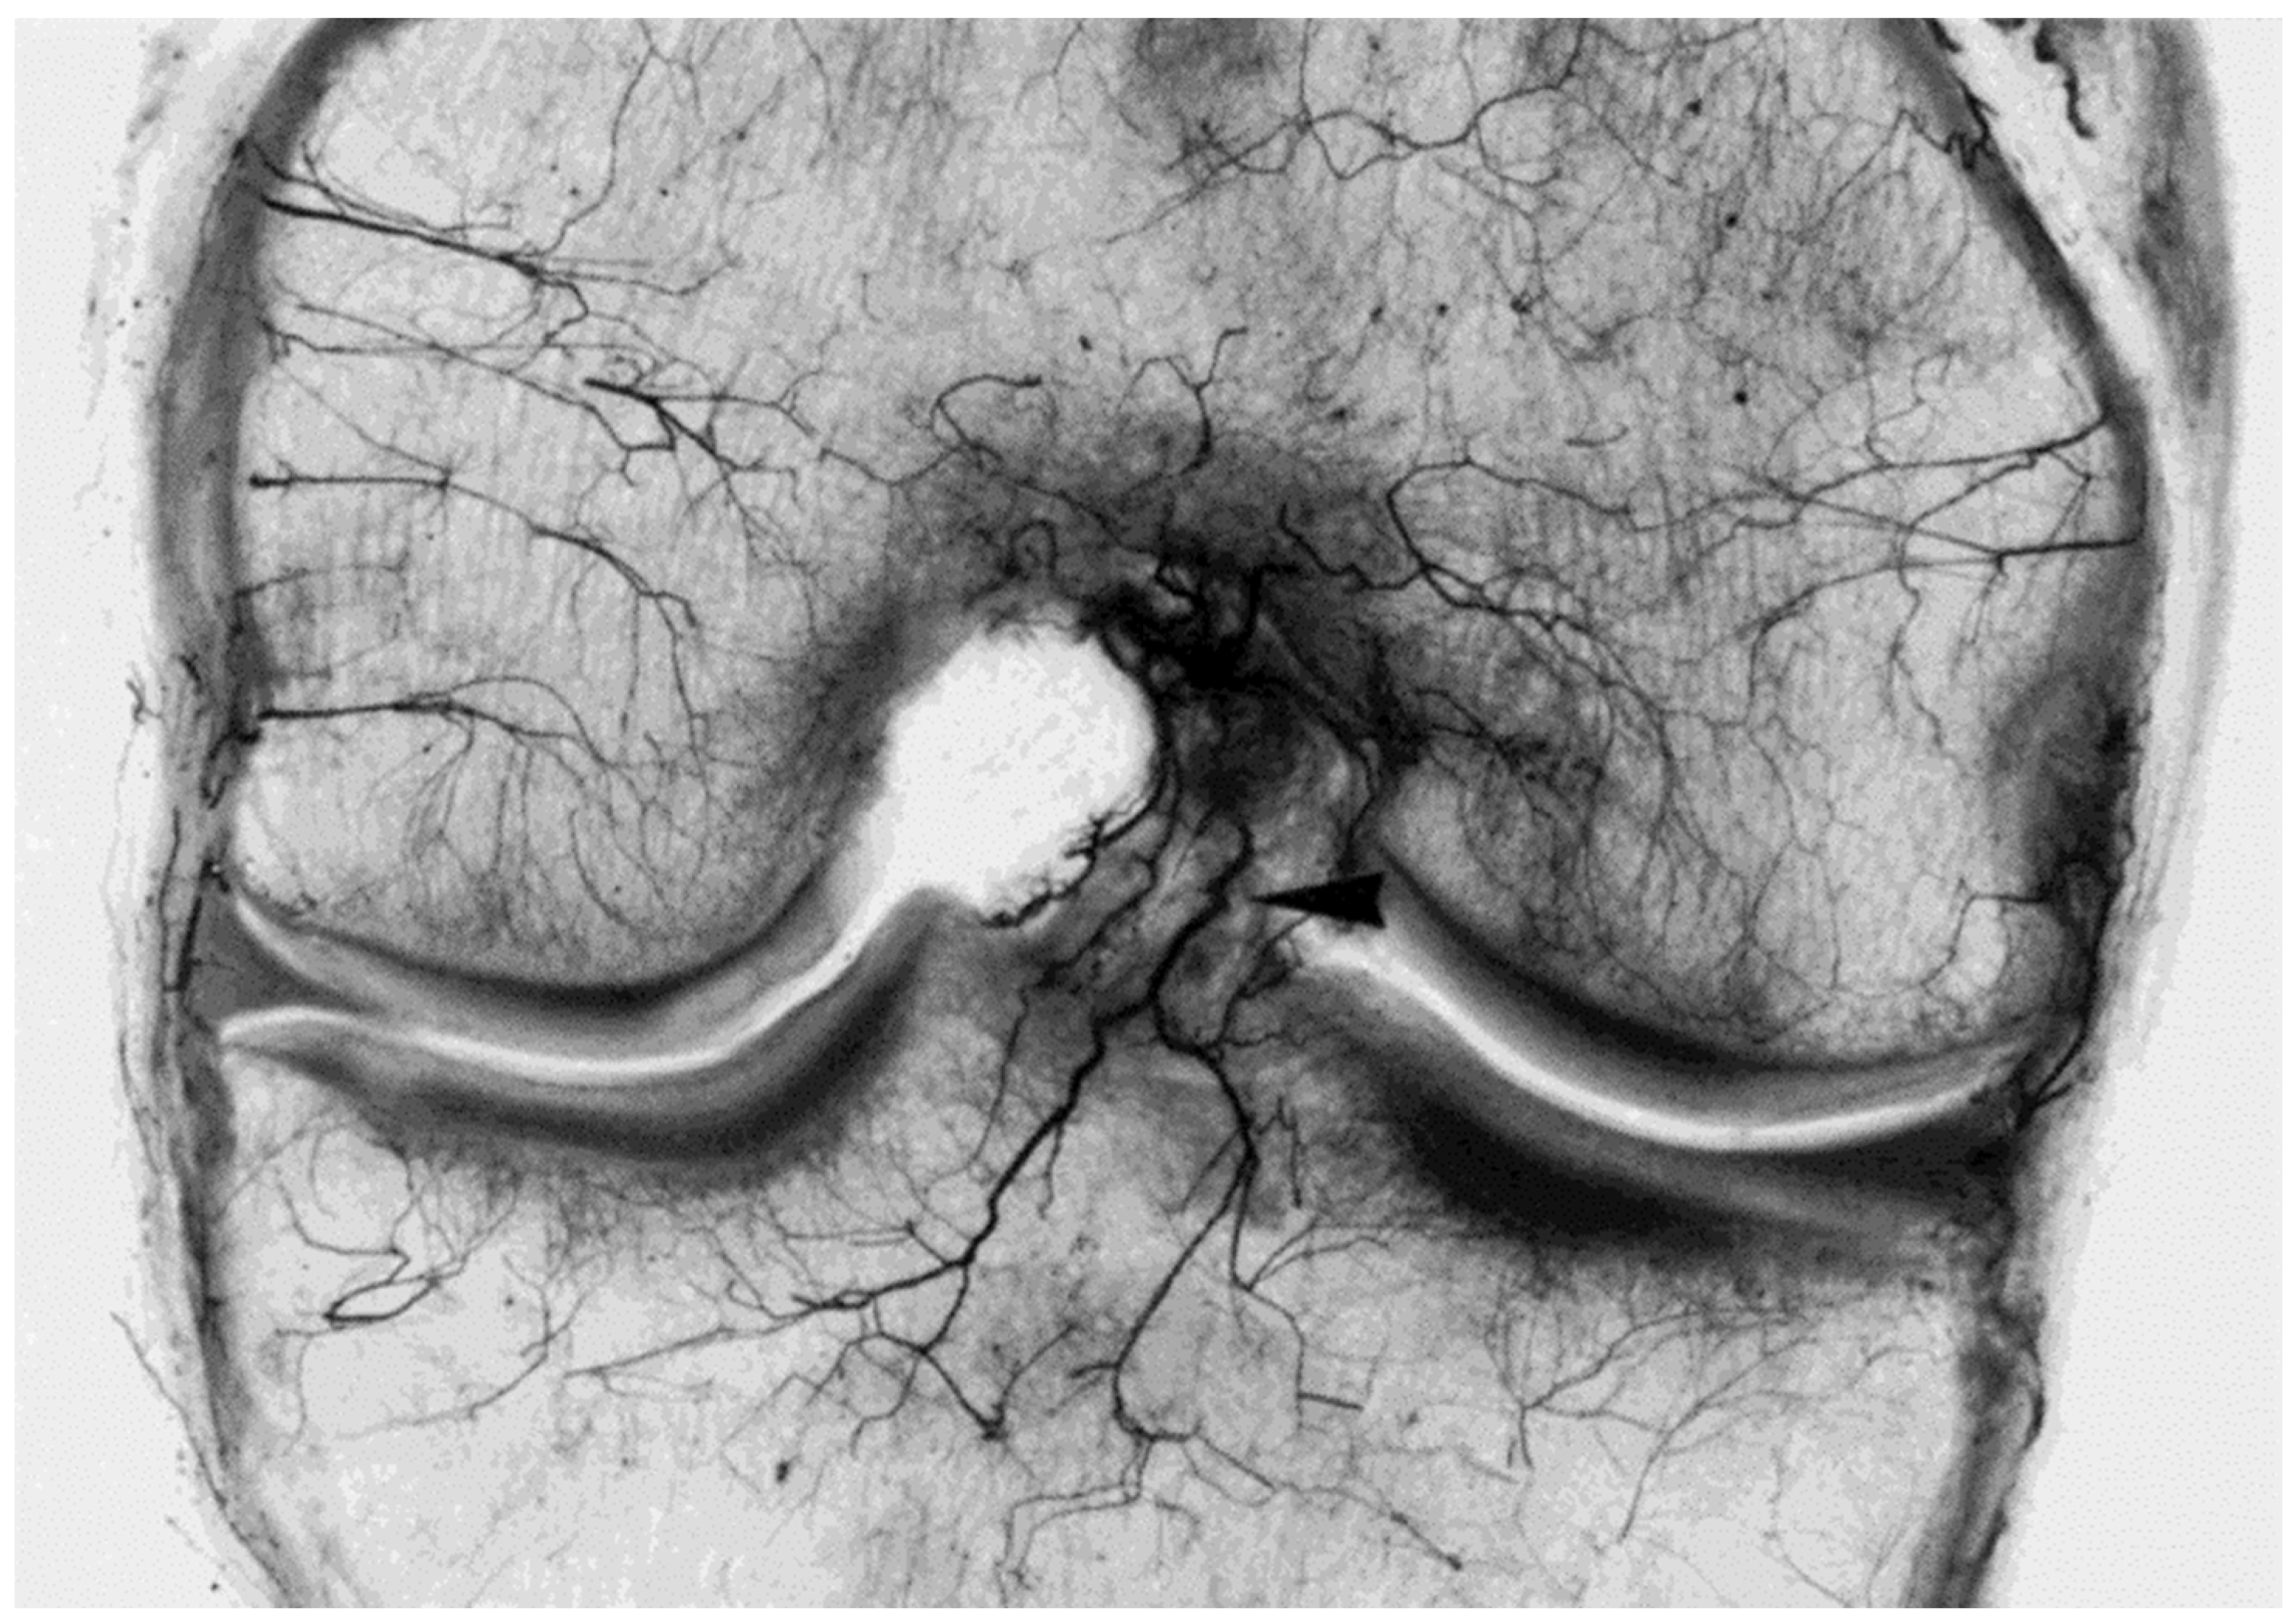

- Scapinelli, R. Vascular anatomy of the human cruciate ligaments and surrounding structures. Clin. Anat. 1997, 10, 151–162. [Google Scholar] [CrossRef]

- Petersen, W.; Hansen, U. Blood and lymph supply of the anterior cruciate ligament: Cadaver study by immunohistochemical and histochemical methods. J. Orthop. Sci. 1997, 2, 313–318. [Google Scholar] [CrossRef]

- Petersen, W.; Zantop, T. Anatomy of the anterior cruciate ligament with regard to its two bundles. Clin. Orthop. Relat. Res. 2006, 454, 35–47. [Google Scholar] [CrossRef] [PubMed]

- Duthon, V.B.; Barea, C.; Abrassart, S.; Fasel, J.H.; Fritschy, D.; Ménétrey, J. Anatomy of the anterior cruciate ligament. Knee Surg. Sports Traumatol. Arthrosc. 2006, 14, 204–213. [Google Scholar] [CrossRef]